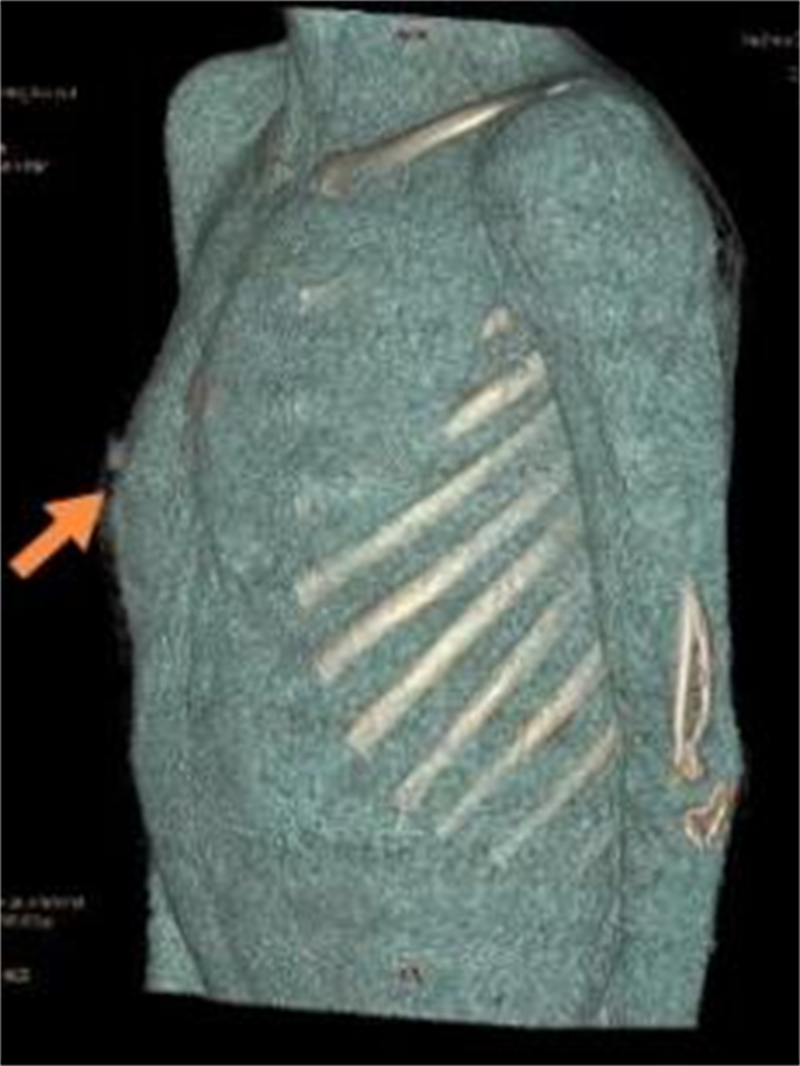

由于肋软骨在X线胸片上不显影,对于肋骨畸形的评价与确诊有局限性,目前多采用胸部 CT加肋骨重建检查。

可以,目前采用悬吊腔镜叉状肋切除术。叉状肋大部分分叉的上部肋软骨发育较细,且生长方向与其他正常肋骨走行角度不一致,这是导致胸壁凸起的原因之一。手术时,通常需切除分叉的上部软骨及分叉的部分硬骨。